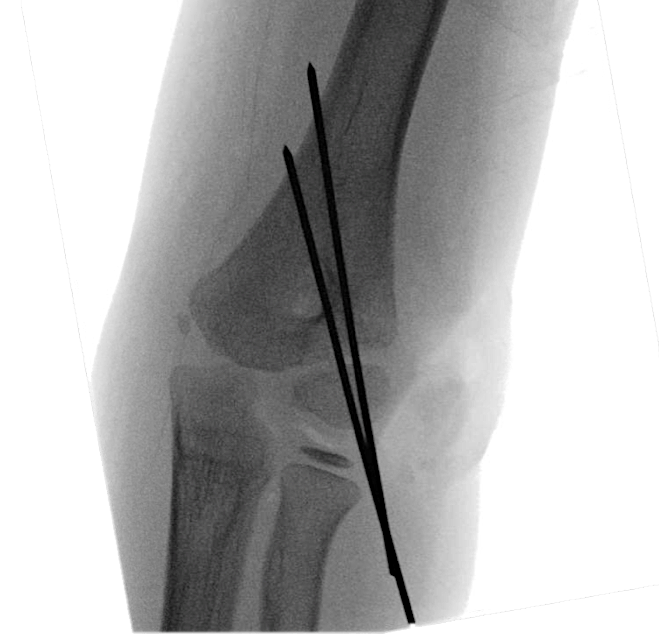

Figure 10: Intraoperative image pinned lateral condyle fracture of Case 2.